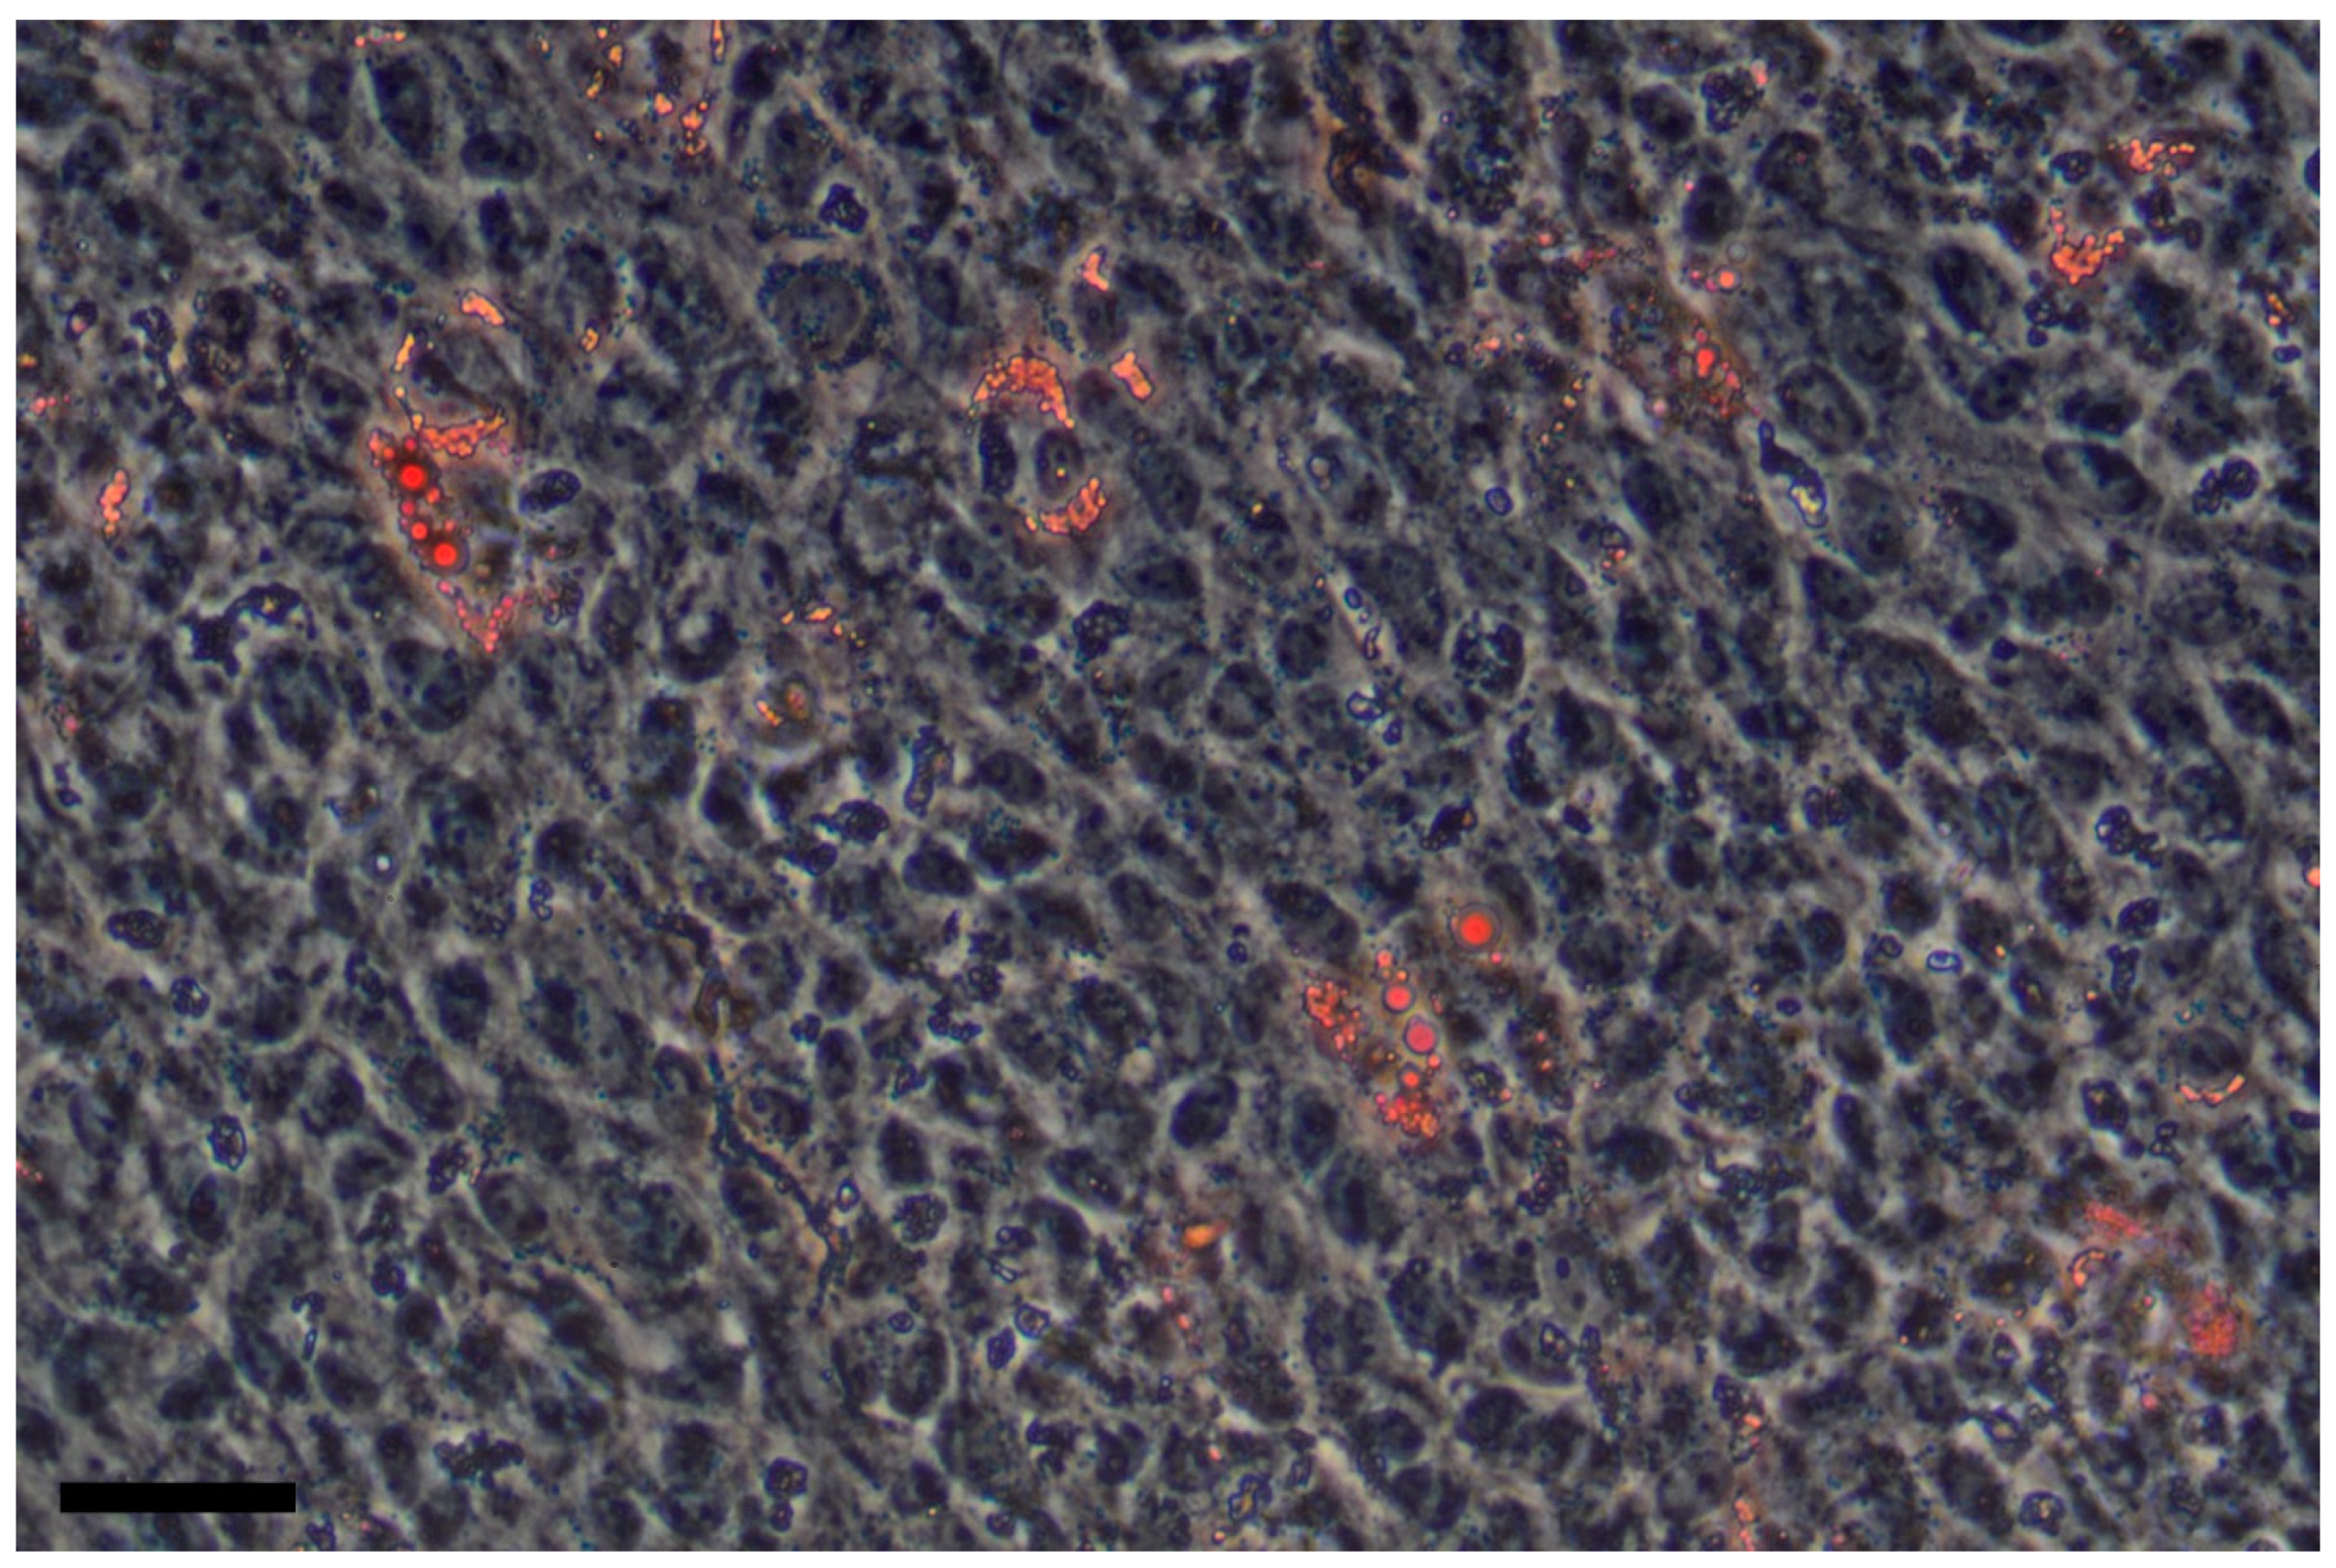

- Herrera, M.B.; Bruno, S.; Buttiglieri, S.; Tetta, C.; Gatti, S.; Deregibus, M.C.; Bussolati, B.; Camussi, G. Isolation and characterization of a stem cell population from adult human liver. Stem Cells 2006, 24, 2840–2850. [Google Scholar] [CrossRef] [PubMed]

- Gerlach, J.C.; Over, P.; Turner, M.E.; Thompson, R.L.; Foka, H.G.; Chen, W.C.; Péault, B.; Gridelli, B.; Schmelzer, E. Perivascular mesenchymal progenitors in human fetal and adult liver. Stem Cells Dev. 2012, 21, 3258–3269. [Google Scholar] [CrossRef] [PubMed]